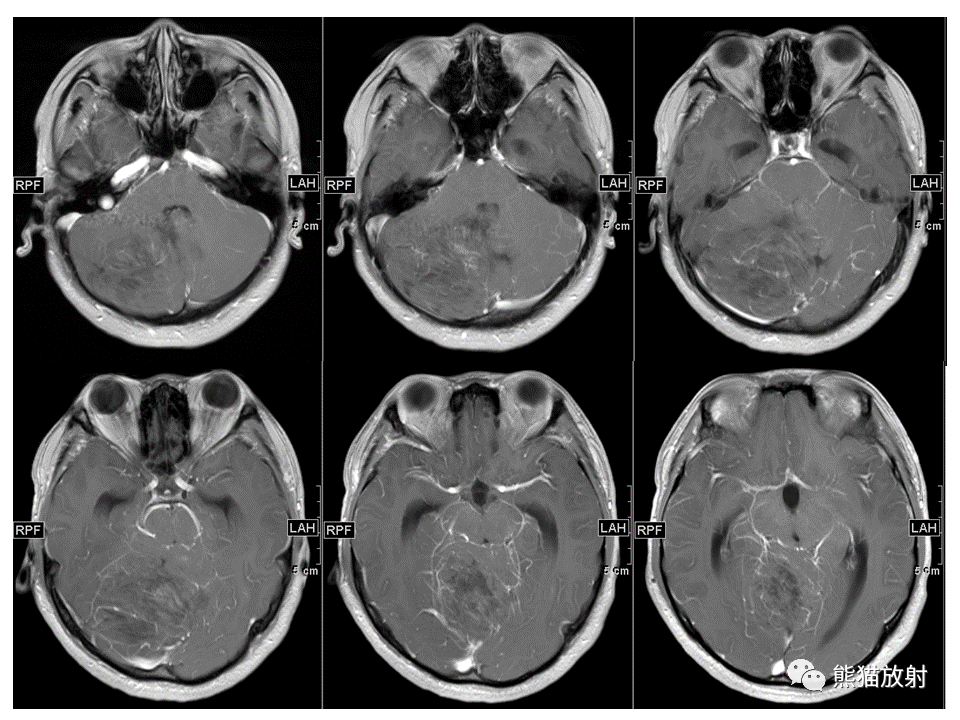

【PPT】小脑发育不良性神经节细胞瘤 VS 成人型髓母细胞瘤-4